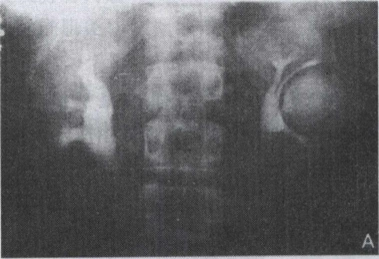

26.患者,男,29岁。发现高血压10年,静脉尿路造影见图。左肾最有可能的诊断是()